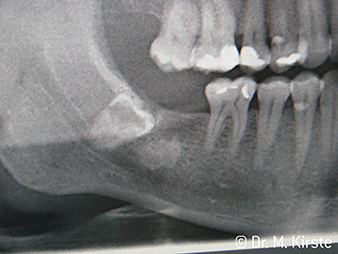

Erstmals kombinieren die Übertragungsinstrumente WS-91 und WS-91 L G die Vorteile von chirurgischen Hand- und Winkelstücken (Abbildung 1). Der auf der Vorderseite erweiterte Winkel zwischen Griffbereich und Bohrerachse erlaubt einen guten Zugang sowohl von bukkal als auch von okklusal über die Zahnreihe (Abbildung 4). Verlagerte Zähne lassen sich bequem trennen (Abbildung 6 und 7). Zudem überblickt der Behandler oder die Behandlerin das Operationsfeld deutlich besser als mit bisher verfügbaren Instrumenten. Dazu Dr. Mario Kirste aus Frankfurt/Oder: „Wenn ich den Winkelstückkopf leicht drehe, kann ich im retromolaren Bereich besonders sicher und schnell arbeiten. Das Instrument hat das Potenzial, die gegensätzlichen Lager der Handstück- und Winkelstückanwender zu versöhnen.“ (Abbildung 2 - 5)